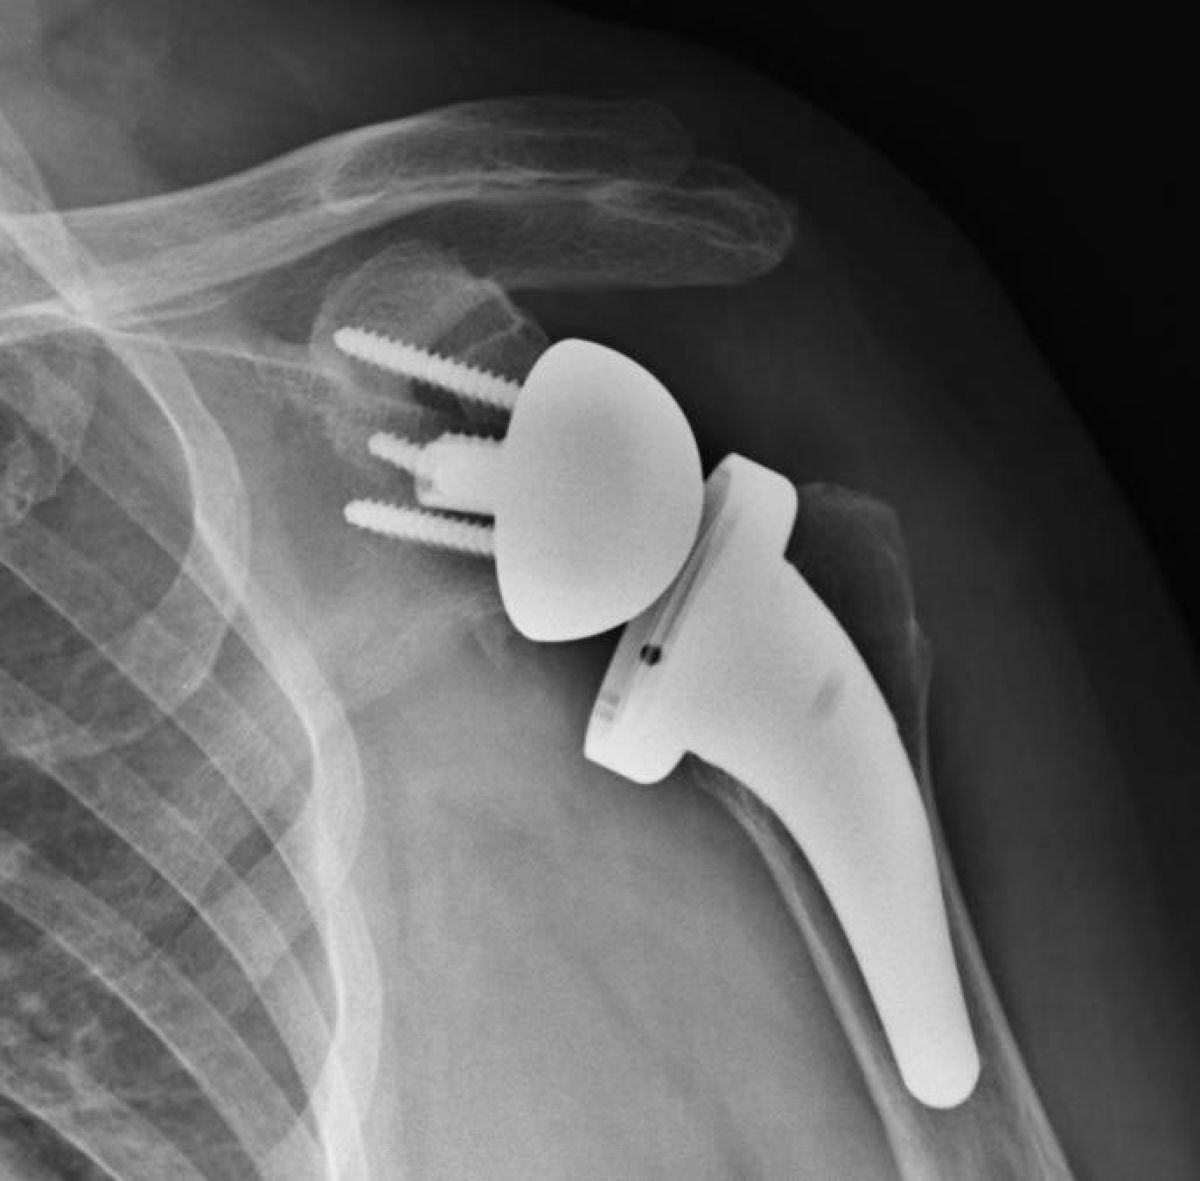

Una protesi alla spalla può innestarsi solo sulla testa dell’omero o sostituire anche la parte glenoidea a livello scapolare: nel primo caso, si parla di protesi spalla parziale, mentre nel secondo caso di protesi di spalla totale.

Questo intervento consiste nell’inversione della normale geometria della spalla, con la sostituzione della concavità della glena con una convessità, rappresentata dalla glenosfera metallica.